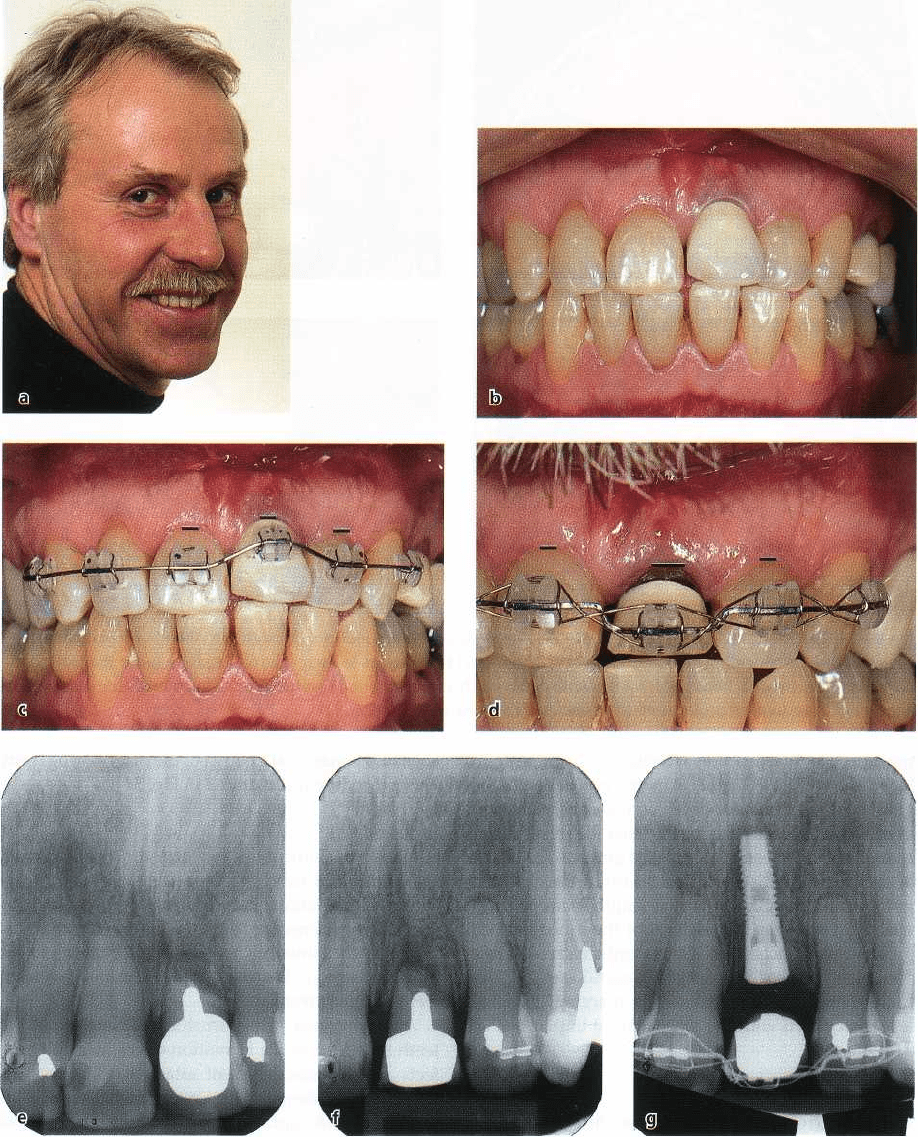

Fig. 31-12. Orthodontic tooth movements into edentulous areas with reduced bone height in compromised mandi

-

ble of adult female patient. During the orthodontic treatment (c-g), the teeth were moved to close three areas of

marked alveolar bone constriction (a,b), most notably in the right first molar area. Note that the impacted third mo

lar erupted spontaneously as the second molar was moved mesially (g). (h) shows final result with bonded six-unit

lingual and two-unit labial retainers.